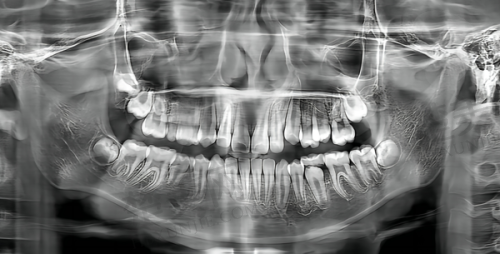

作为松原市首批引入数字化诊疗技术的机构之一,精技口腔配备了韩国 CBCT 影像系统、丹麦 3D 口扫仪、美国 STA 麻醉仪等设备。这些设备让种植牙误差可控制在 0.1 毫米以内。

它的核心技术亮点颇多。数字化导航种植通过 3D 导板模拟手术路径,减少了创伤,2024 年种植体存活率达 98.2%。即刻负重种植更是厉害,半口或全口种植可当天完成,实现咀嚼功能,有患者反馈“当天就能吃饭”。儿童牙科也有特色,专设儿童游乐区,医生还有哄娃技巧,同时提供涂氟、窝沟封闭等预防性服务。